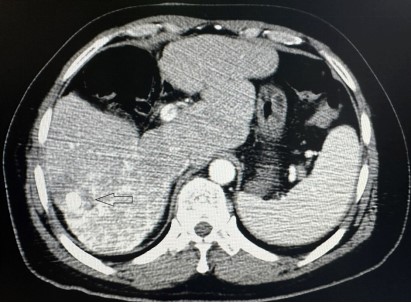

图3 消融术后肿瘤完全坏死,周围可见低密度安全边缘(黑色箭头)

3月12日李建军主任医师为患者行肝动脉化疗栓塞术治疗,术中造影明确诊断为原发性肝癌,术后行平扫CT可见肿瘤内碘油沉积。因肿瘤消融是首次在拉萨市人民医院开展,并需要在CT引导下操作,放射科旺堆主任积极协调科室医生、护士和技师,表示全力支持。导管室护士白玉及德吉卓嘎积极准备术中所需药品及材料。3月19日,由觉旦次仁技师操作CT,旦巴旺秋及格桑元旦医师辅助,白玉及德吉卓嘎护士配合下,李主任为患者成功行肝癌消融术,术中患者无特殊不适,手术时长30分钟,没有出血等并发症,患者安返病房。术后第1天患者也未诉任何不舒服,已可下床活动。